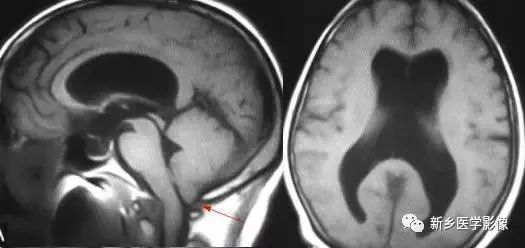

❷ 小脑扁桃体下疝畸形

又称Chiari's畸形,即小脑扁桃体下移到椎管内,延髓、四脑室延长并部分向下移位。可分为3型。各型均常有脑积水表现。

Ⅰ型:若仅有小脑扁桃体下移。扁桃体下缘低于枕大孔连线5mm以上,无脑干及四脑室改变者为Ⅰ型。

Ⅱ型:除小脑扁桃体下移外,同时有四脑室部分或全部降入枕大孔以下者为pⅡ型。

Ⅲ型:全小脑及四脑疝入枕大孔以下者为Ⅲ型。